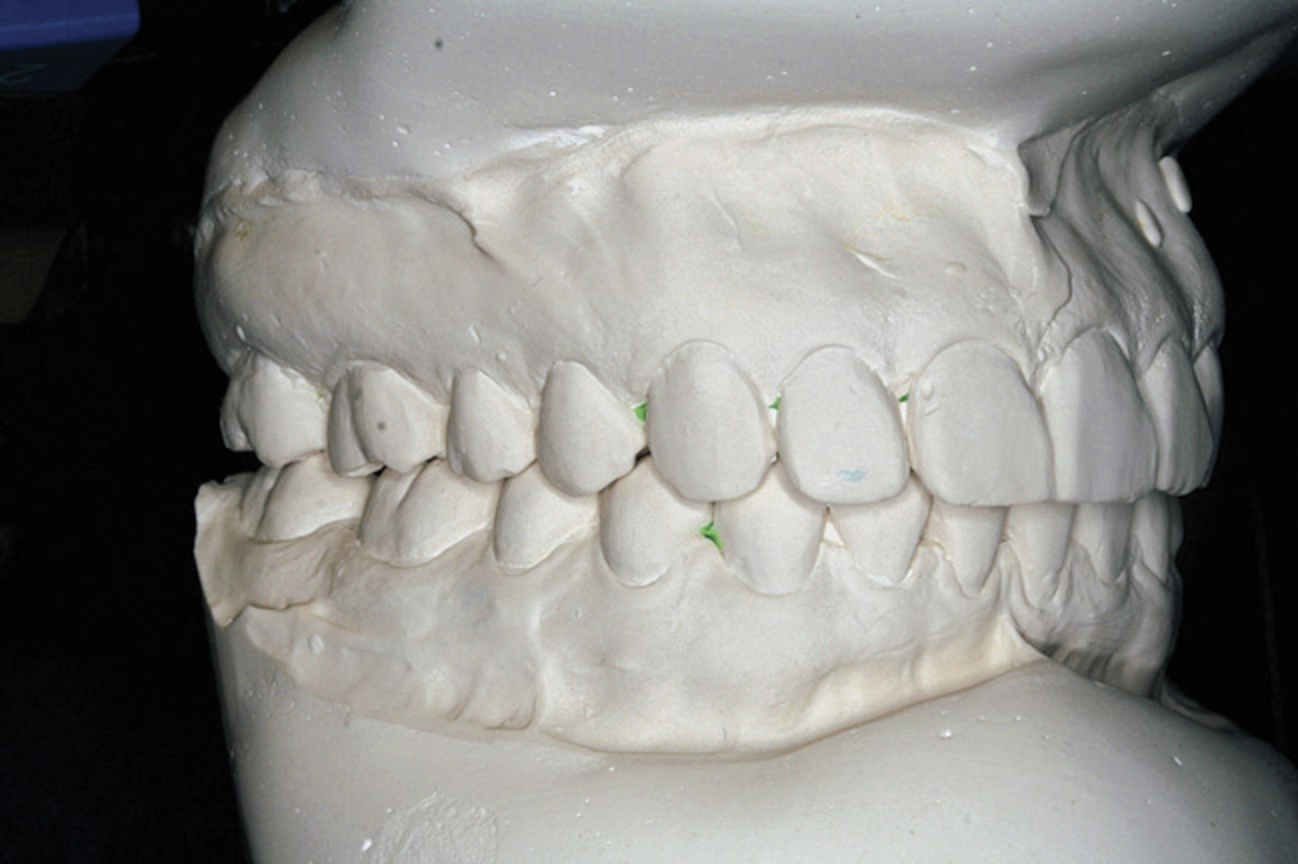

Figure 7A  This case is an example of the importance of evaluating the bite with the joints seated in a stable position. Orthodontic treatment was rendered to correct a "deep overbite" and trauma to the maxillary incisors. A) Handheld models in maximum intercuspation at beginning of treatment. The deep overbite is apparent.

Figure 7A

Figure 7B  This case is an example of the importance of evaluating the bite with the joints seated in a stable position. Orthodontic treatment was rendered to correct a "deep overbite" and trauma to the maxillary incisors. B) Handheld models showing correction of the deep overbite after orthodontics has been completed. The patient complained of "jaw" discomfort after orthodontic treatment.

Figure 7B

Figure 7C This case is an example of the importance of evaluating the bite with the joints seated in a stable position. Orthodontic treatment was rendered to correct a "deep overbite" and trauma to the maxillary incisors. C) Models mounted in CR after use of a superior repositioning splint to stabilize the joints. With stabilized joints, the true malocclusion is uncovered. The patient went back into orthodontic treatment and required mandibular advancement surgery.

Figure 7C

Figure 7D  This case is an example of the importance of evaluating the bite with the joints seated in a stable position. Orthodontic treatment was rendered to correct a "deep overbite" and trauma to the maxillary incisors. D) Models mounted in CR after retreatment.

Figure 7D